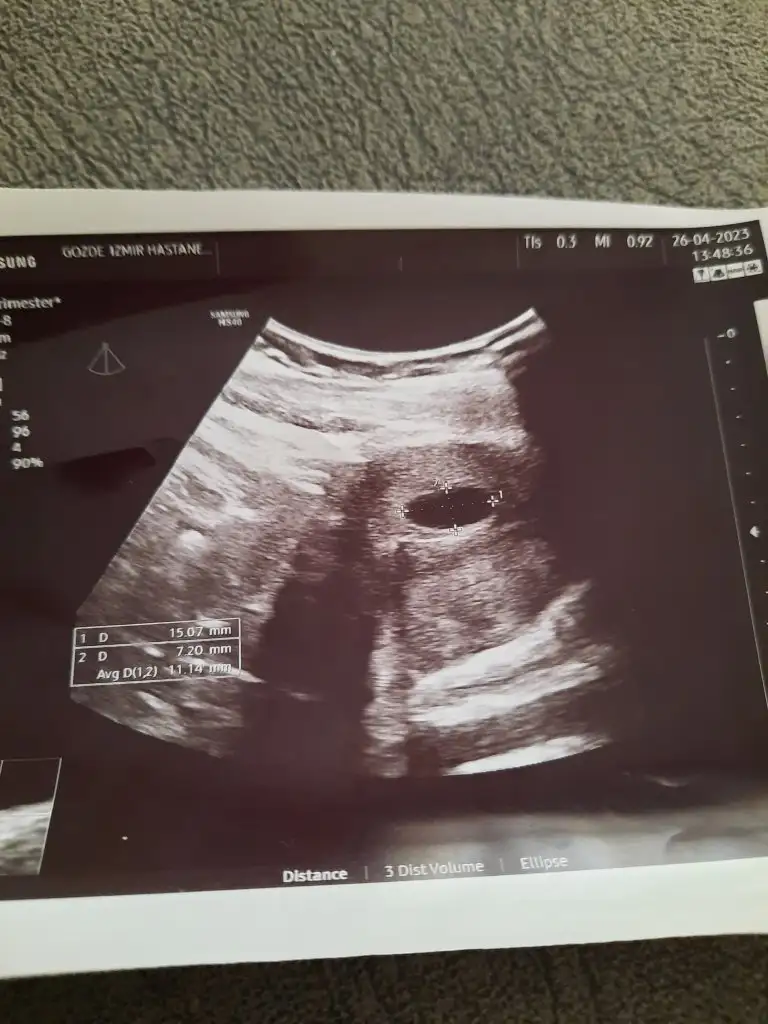

Çok güzelMerhaba teyzeleribiz 7 haftalik olduk bugün kalp atışı duyduk çok şükür dünyanın en güzel duygusuymus

Kız yerim minnoşMerhaba teyzeleribiz 7 haftalik olduk bugün kalp atışı duyduk çok şükür dünyanın en güzel duygusuymus

Oy masallah ne guzel yatmis annesinin karnina :)Merhaba teyzeleribiz 7 haftalik olduk bugün kalp atışı duyduk çok şükür dünyanın en güzel duygusuymus